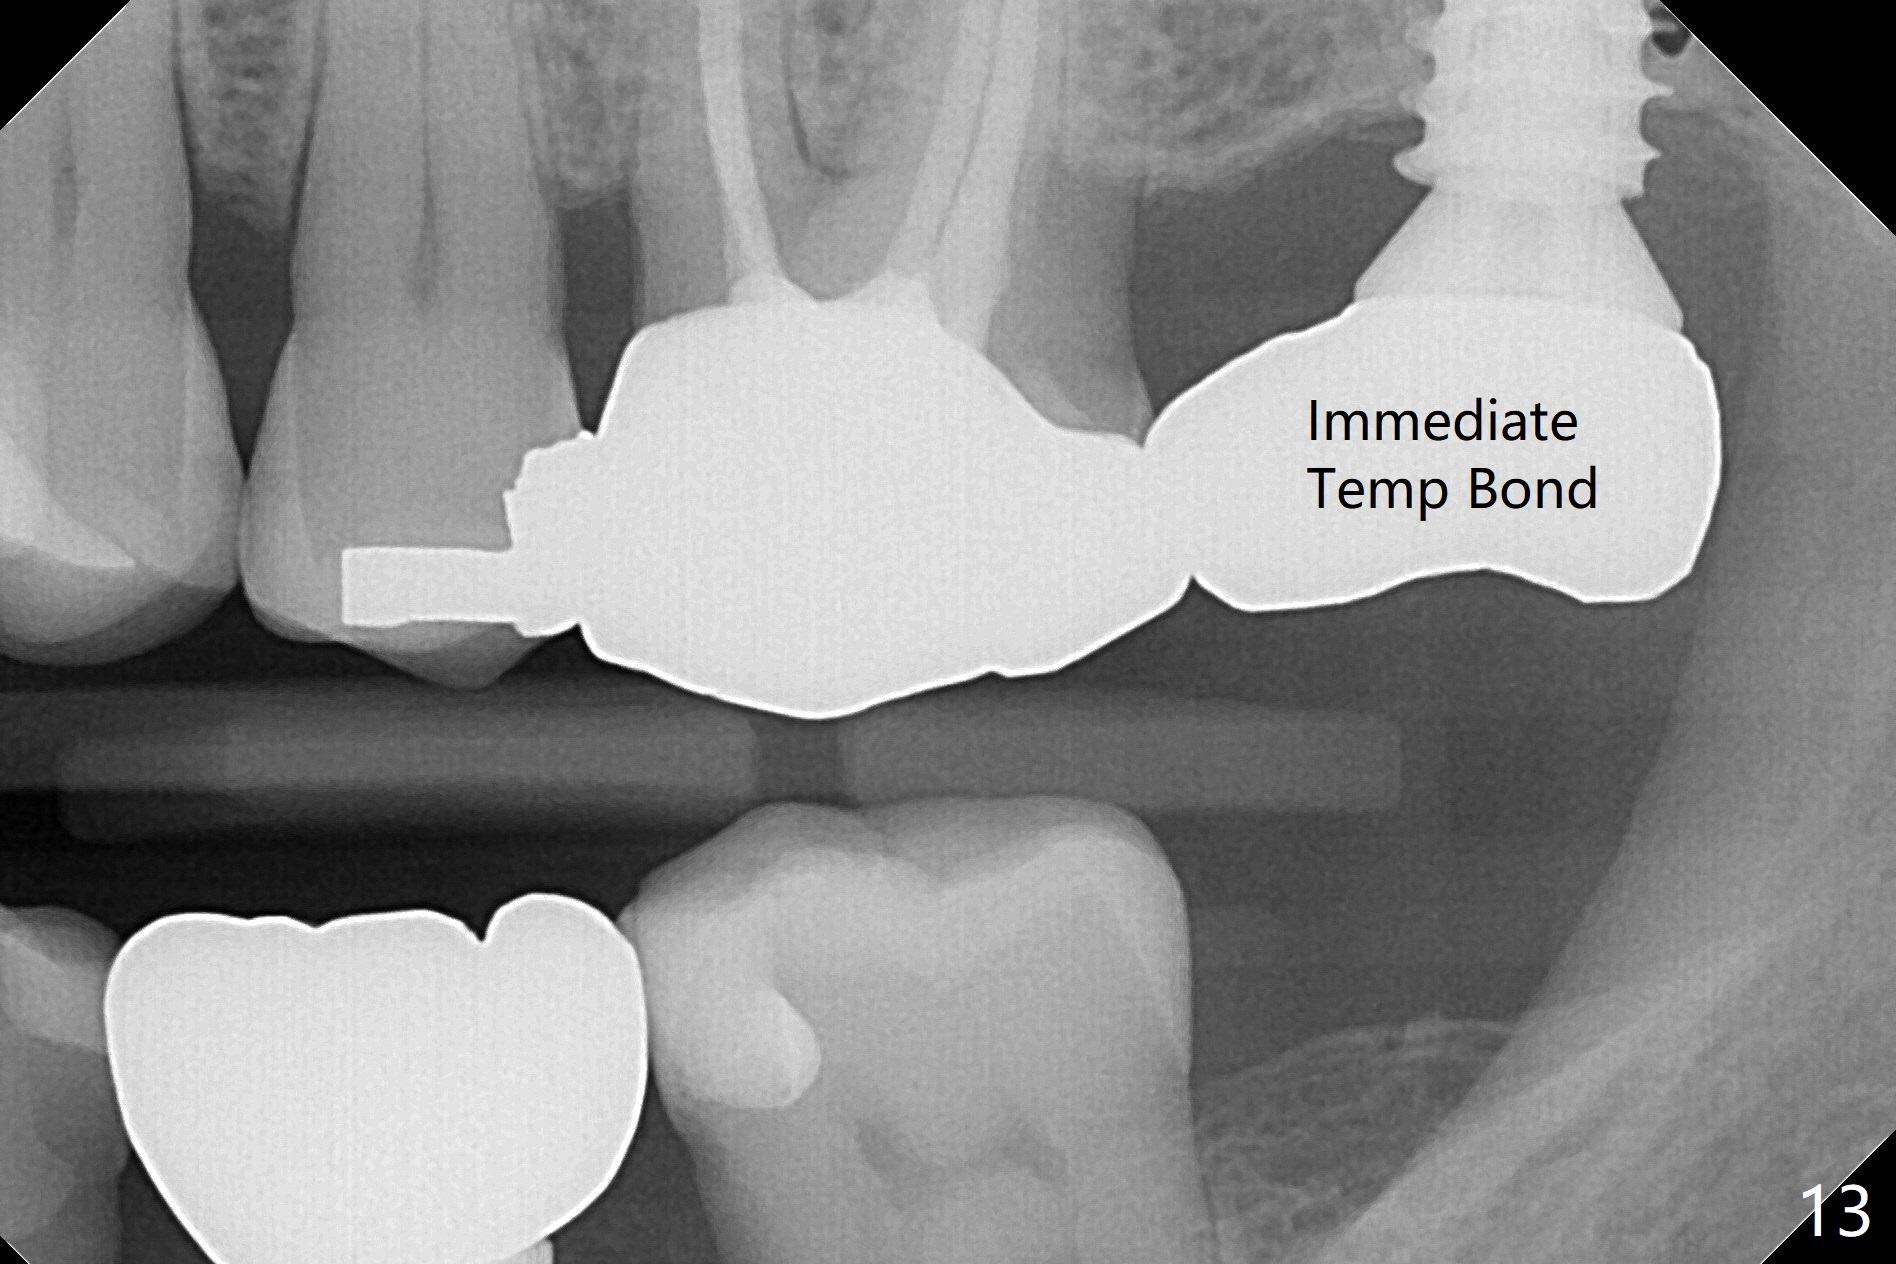

The ridge is pointed at the site of #15 (Fig.1). A 1.2 mm initial drill is used to start osteotomy for 10 mm, followed by an incision over the ridge mesiodistally for ~ 8 mm. After tapping the #15 C blade, the 1st Bone Expander 1.0/1.6 mm) is inserted for ~ 11 mm (Fig.2, 20 Ncm). Bone expansion continues until #4 Expander (2.4/3.7 mm, Fig.3). When 4x11 mm and 4.5x11 mm dummy implants are placed (Fig.4), insertion torque remains 20 Ncm. Following placing allograft with 3-4 amalgam carriers, a 5x11 mm IBS implant is placed with 20 Ncm (Fig.5,6). In fact the implant turns when an abutment is placed. When the implant is re-inserted, torque decreases to 10 Ncm. Instead a healing screw is placed. The low torque value is due to soft bone and failure to underprep. #4 Expander (Fig.3) seems larger than 4.5 mm implant (Fig.4). #3 Expander (1.7/3.1 mm) should have been used prior to definitive implant placement. The implant appears to have osteointegrated 3 months postop (Fig.7); impression is taken. The bone density at the crest increases 1.5 years post cementation (Fig.8 *, as compared to Fig.6), although there is mild bone loss. Implant placement should be deep when bone expansion is carried out. The tooth #14 develops a buccal fistula, corresponding to periapical radiolucency of the mesiobuccal root (Fig.9 white >). The abutment of #15 may be incompletely seated (black <). PA taken when RCT of #14 is finished does not show the incomplete seating of the abutment (Fig.10). Since there appears no history of abutment screw loosening, the abutment is not reseated when #14 is prepared for crown. Recall 3 years 7 months post cementation shows incomplete seating of the abutment (Fig.11 >). After crown proximal reduction (Fig.12 *) and clockwise turn of the crown, the abutment appears to be completely seated. When the case returns from lab, the separate crown and abutment cannot be connected to the fixture because of soft tissue adaptation and change in a month. The abutment is reseated to the fixture analog in the model and the crown is recemented with temp bond (in case of misalignment) while making sure that the crown has the best proximal contact with the neighboring crown. With the abutment and crown in a unit, it is much easier to reseat the abutment with normal proximal contact. The torque is 20 Ncm. The access hole is closed with Cavit.